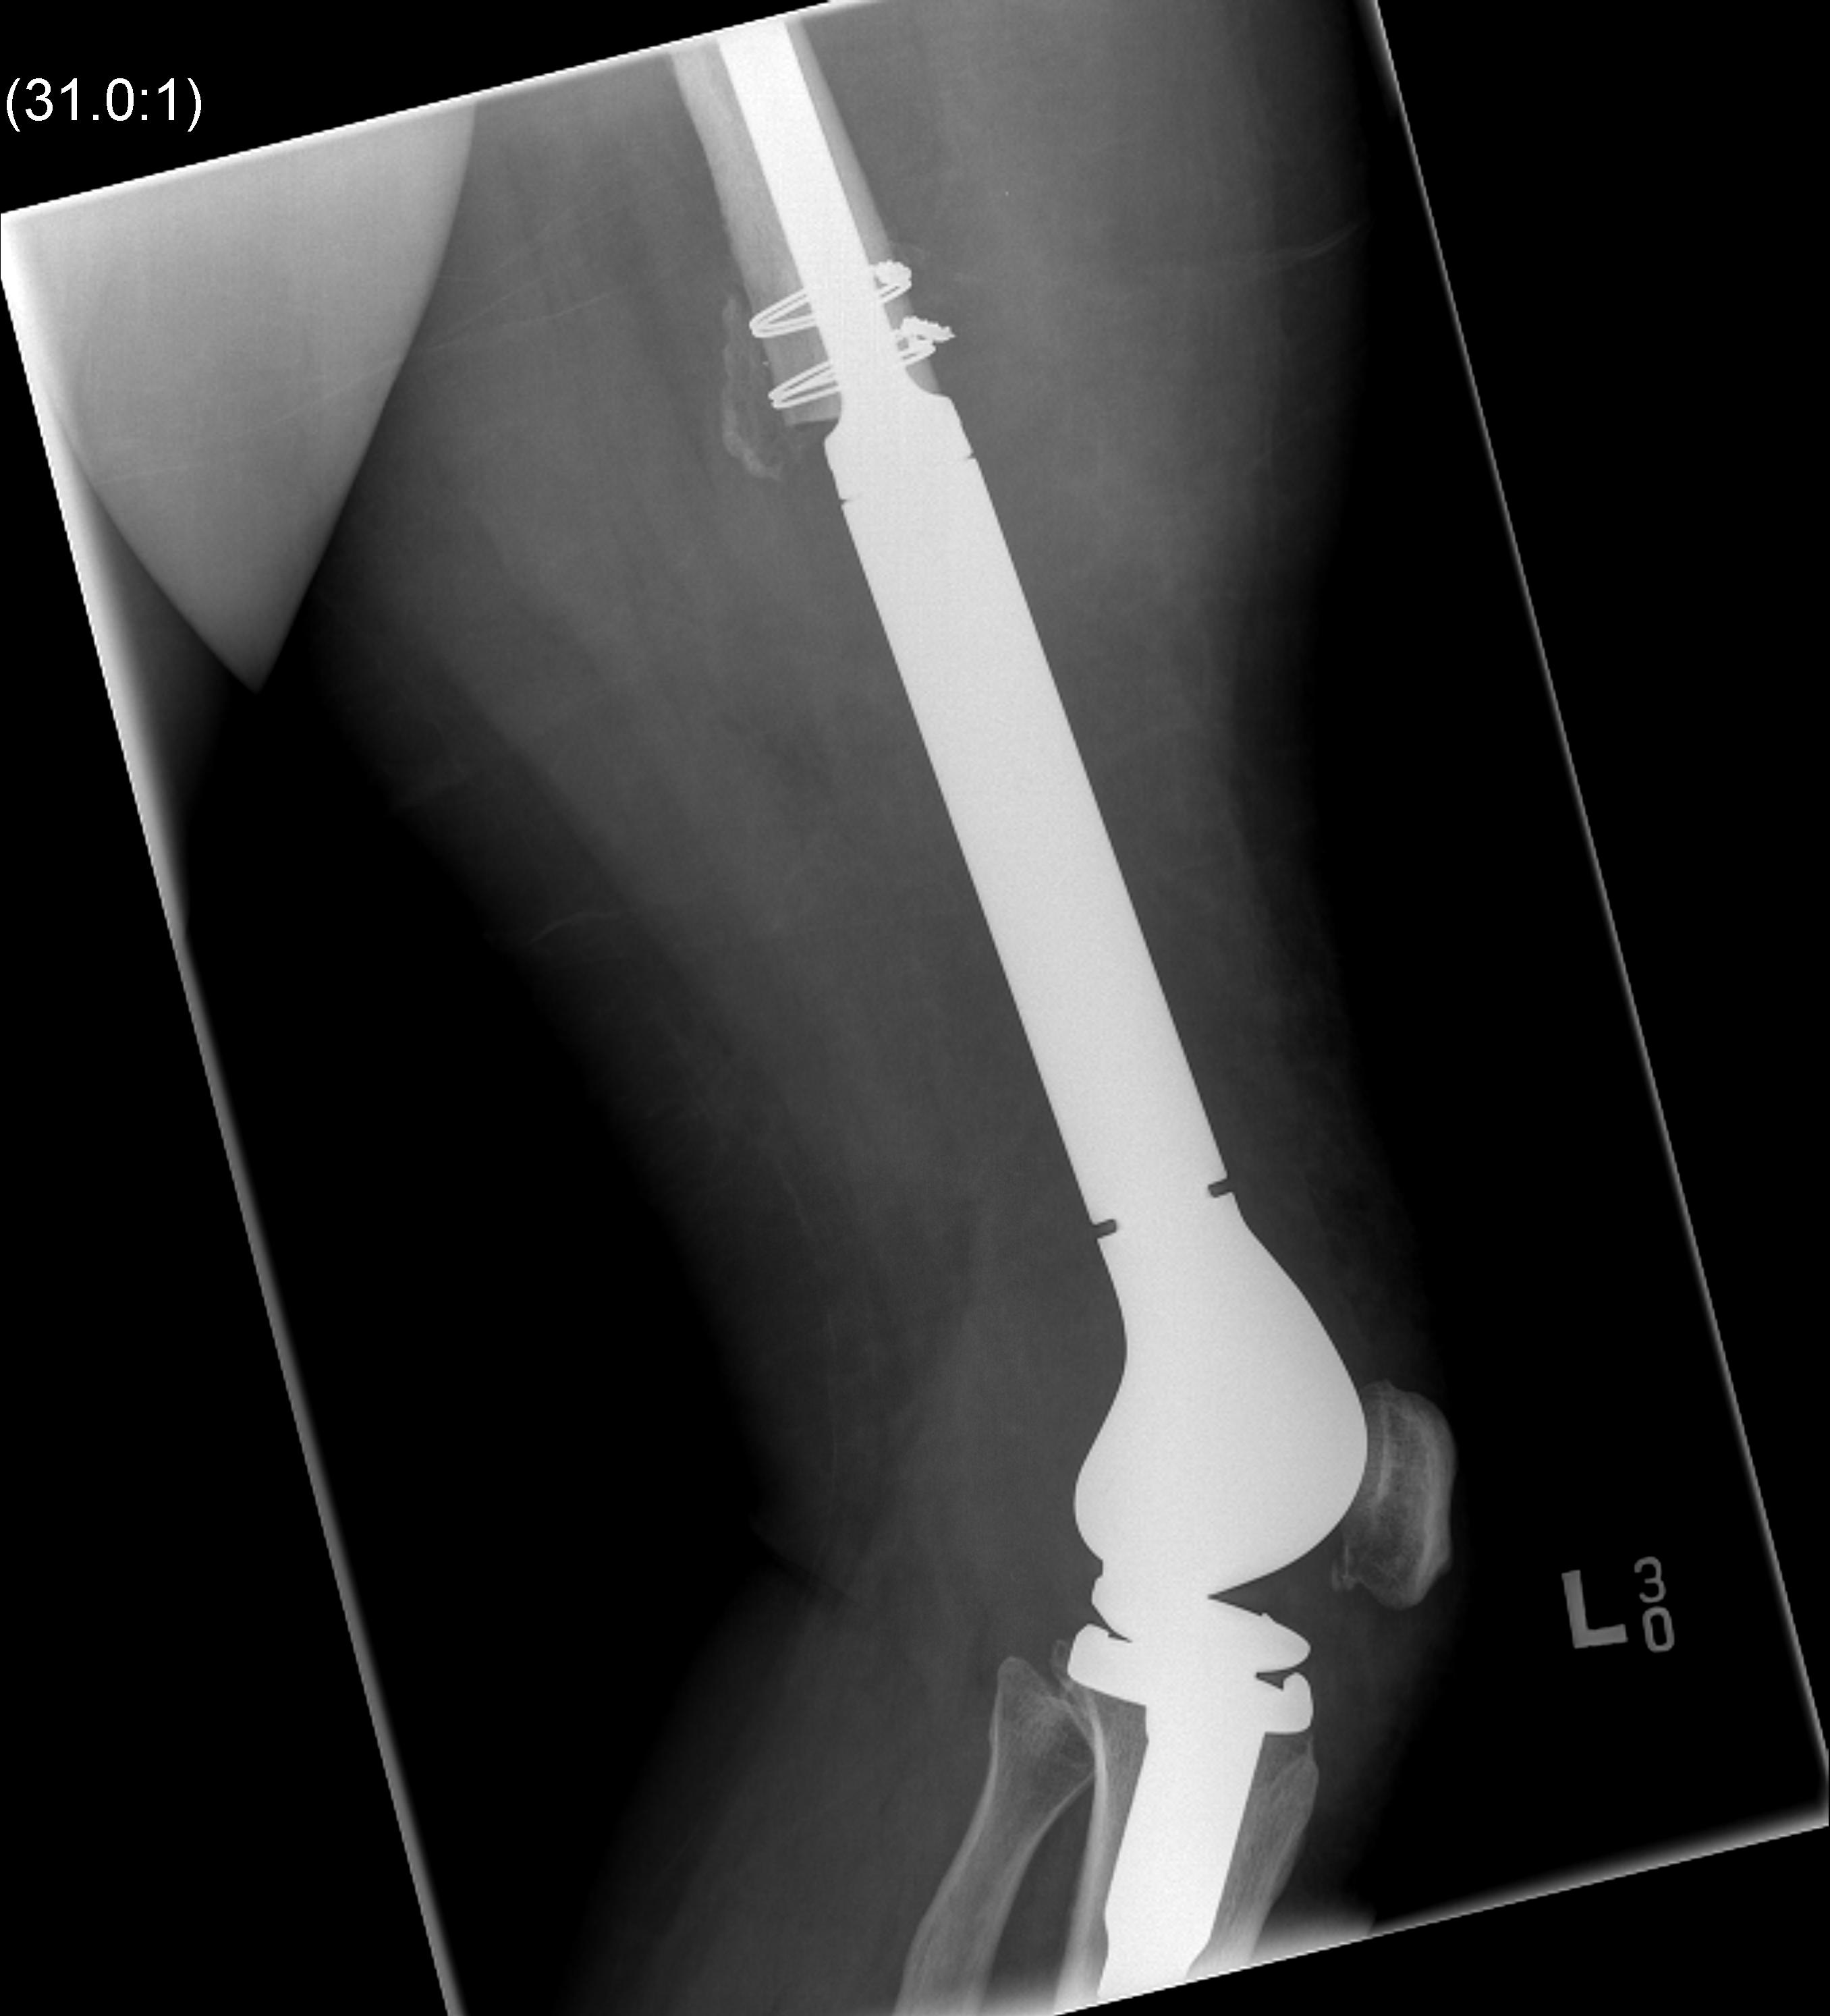

Post distal femoral osteosarcoma resection